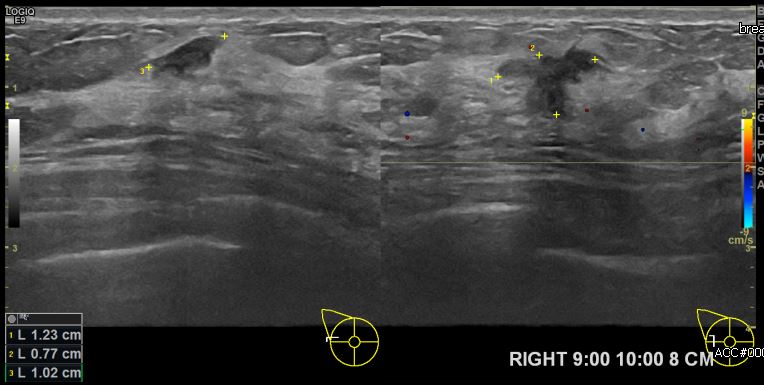

상기환자 양측 유방의 멍울로 내원하신 50대 여성분으로 본원 초음파상 우측 9시에서

10시 방향에서 8cm 떨어진 거리의 의심스러운 멍울 조직검사 시행하여 우측 침윤성

유관암 진단되었습니다.